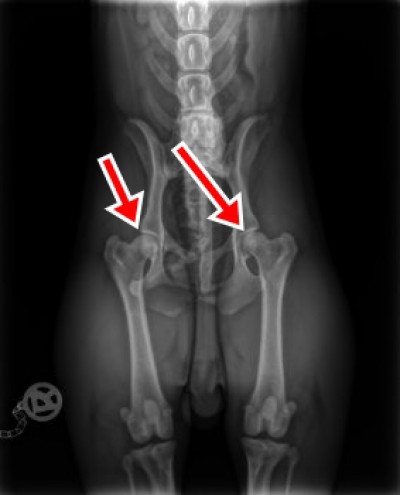

Hüftgelenkdysplasie der Französischen Bulldogge

Die Hüfgelenkdysplasie (HD) ist die häufigste Erbkrankheit des Skelettes der Hunde, sie betrifft alle Rassen und Mischlinge. Hier ist das Kugelgelenk, welches aus der Hüftpfanne (Acetabulum) und des Oberschenkelkopfes (Femurkopf) besteht, von dysplastischen Veränderungen betroffen, die sich im Laufe des Lebens durch Verschleiß verstärken und nicht heilbar sind. Die HD wird multifaktorell vererbt und ist trotz strenger Diagnose- und Selektionsmaßnahmen nur schwer kontrollierbar, da auch gesund ausgewertete Tiere Träger der Krankheit sein und diese vererben können.

Neben der genetischen Disposition spielen auch Einwirkungen aus Belastung und Fütterung eine geringfügige Rolle, die die pränatale Entwicklung des Hüftgelenks beeinflussen können. Hauptursächlich muss aber sicherlich die Erbanlage für die Lockerheit des Gelenkes gesehen werden. Ein genetisch HD-gesunder Hund wird durch unsachgemäße Ernährung und Bewegung als adulter Hund kaum zu schweren Deformationen neigen.

Die Rasse Französische Bulldogge ist wie der Mops und die Englische Bulldogge von der HD stark betroffen. Die Krankheit wird aber wegen ihrer „weichen“ Symptome, die bei dem kleinen, stark bemuskelten Hund erst bei hochgradigen Veränderungen auffällig werden, überwiegend ignoriert.

Viele Bullys zeigen bei stabiler Wirbelsäule in Verbund mit mittlerer HD keine deutlichen Anzeichen von Schmerzen oder Bewegungseinschränkungen, da der Bully, anders als beispielsweise der Dobermann seine Fortbewegung hauptsächlich aus der Kraft der Vorderhand holt.